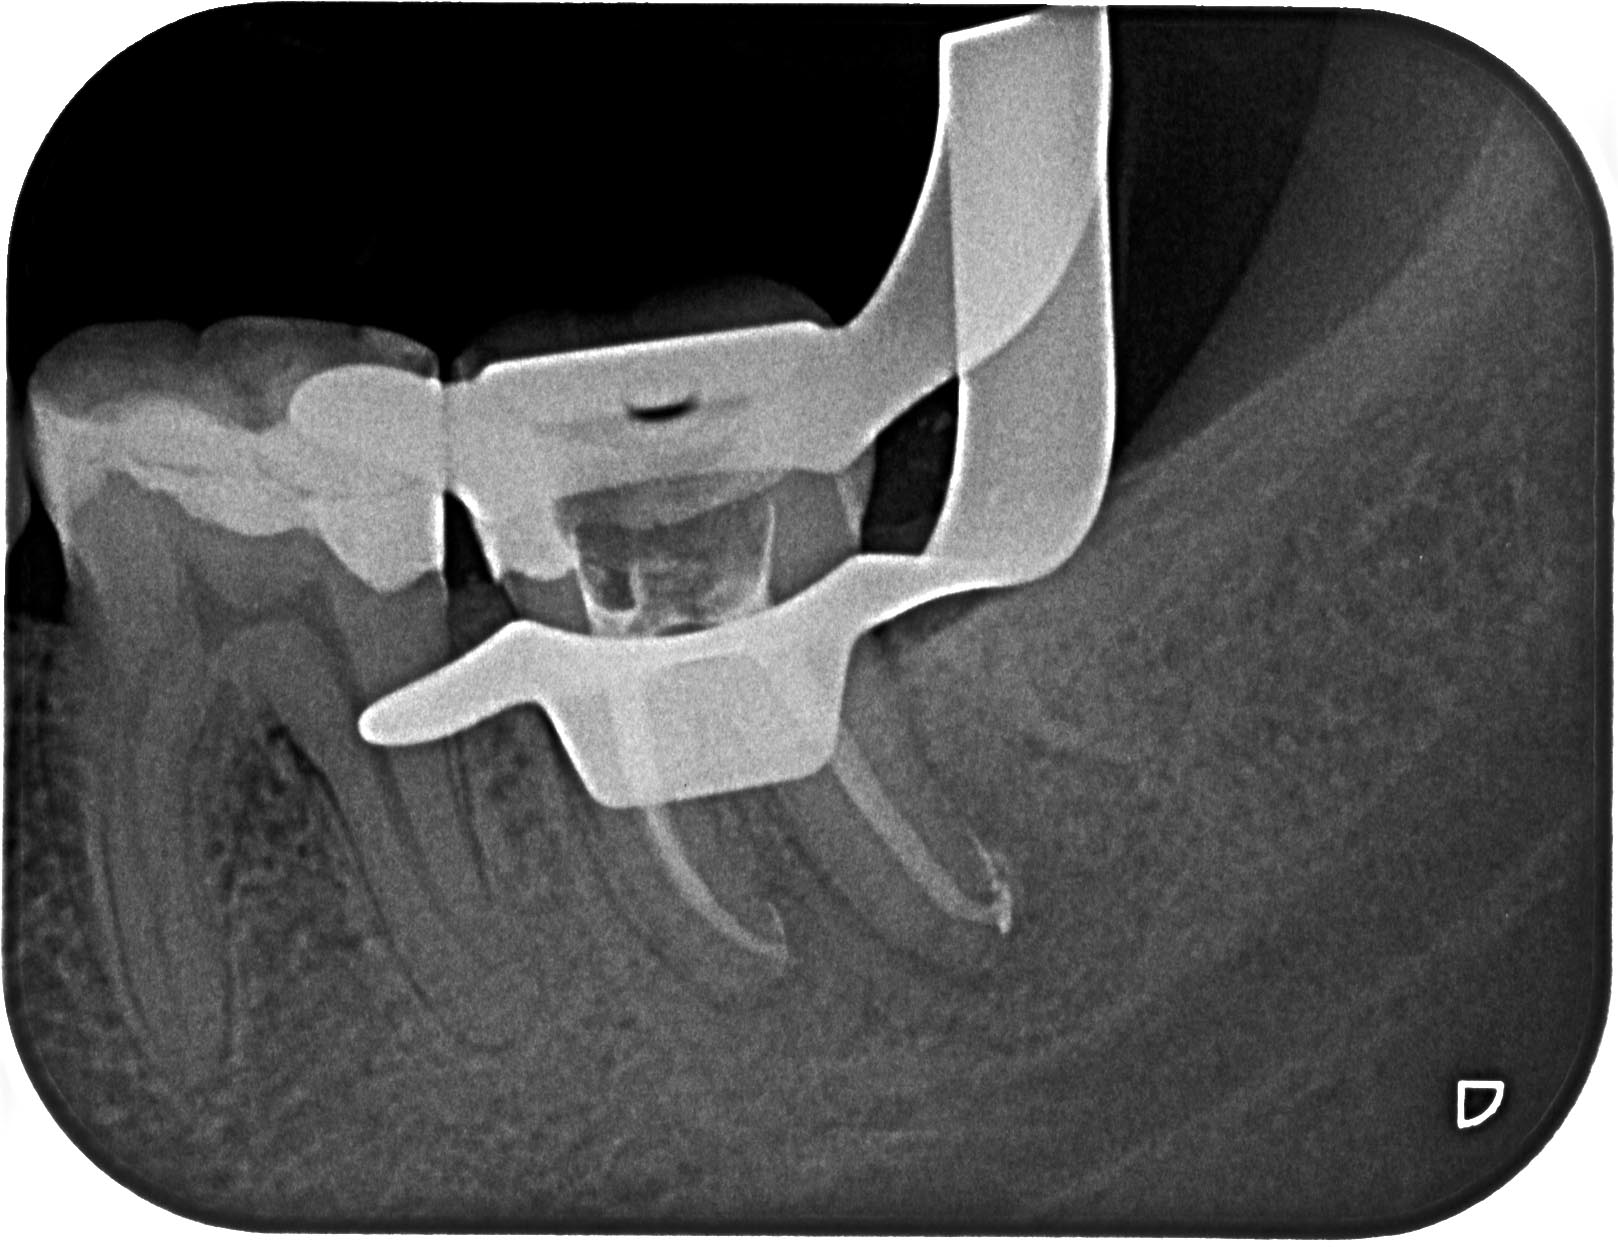

AA-1-2 Veröffentlicht 11. September 2012 am 1618 × 1247 in Recall des Tages – Zahn 37 mit apikaler Aufhellung